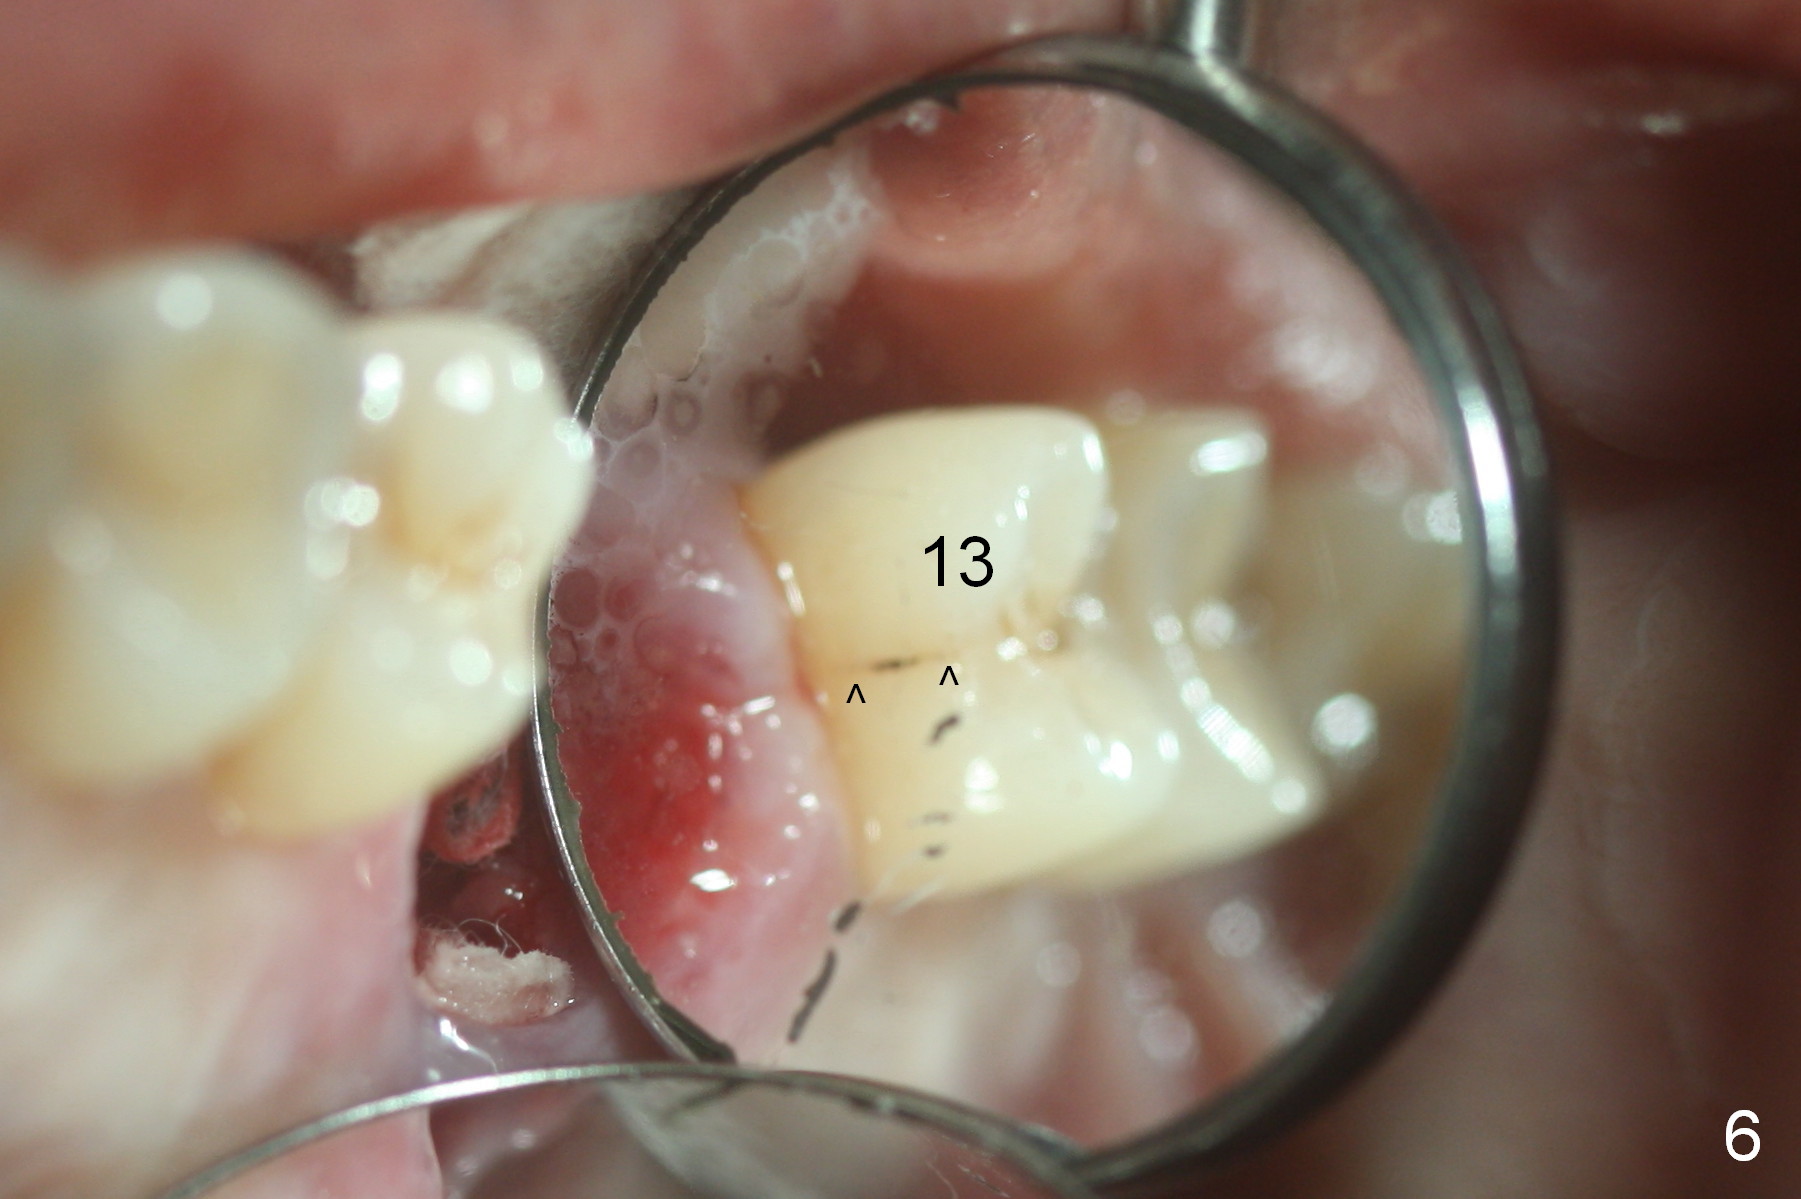

When the tooth is extracted, the lingual crack line (Fig.4 white <) is contiguous with the mesiobuccal one (black >). The latter corresponds to the white arrowheads in Fig.2. In all the crack line is extensive. The buccal and palatal plates are defective coronally. The large granulation tissue in the furca (Fig.5 *) suggests bone loss in the crestal septum. Most surprising is a crack line in the distal surface of the tooth #13 (Fig.6 ^) and in the mesial surface of #15 (Fig.7). Night guard will be fabricated after an implant crown is cemented at #14.